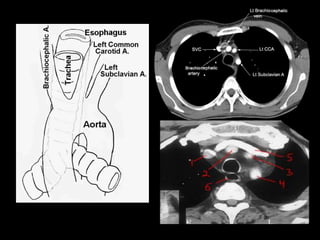

• #11 The relations of the arch to the airway and esophagus – shown in (a) anterior–posterior and (b) left lateral views – must be appreciated. In particular the proximity of the esophagus to the distal arch adjacent to the subclavian should serve as a warning to the surgeon not to be too aggressive with sutures posteriorly when reconstructing the distal arch. Because of this relation, many surgeons prefer to completely divide the arch at the level of the subclavian to permit direct visualization of each and every suture as placed.